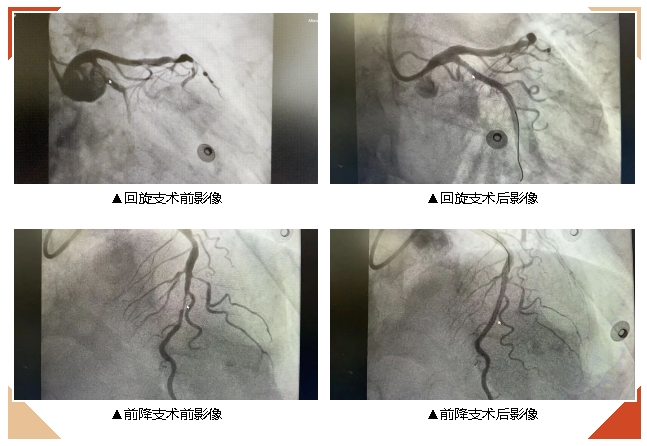

12月26日手术如期实施,由心内科阮景明主任医师指导,林庆主治医师、潘为涛副主任医师执行,同时由专业的导管室护师吴文永及技师团队协作,以保障手术的顺利进行。术中造影见回旋支近段几乎完全闭塞,前降支中段重度狭窄,先后于回旋支及前降支各植入药物洗脱支架1枚。

从冠脉造影开始到手术结束仅历时33分钟,造影剂总用量仅90ml。团队的默契配合,完成术前既定的“三减”方案。术中患者生命体征平稳,无任何不适。术后安返心内科病房。